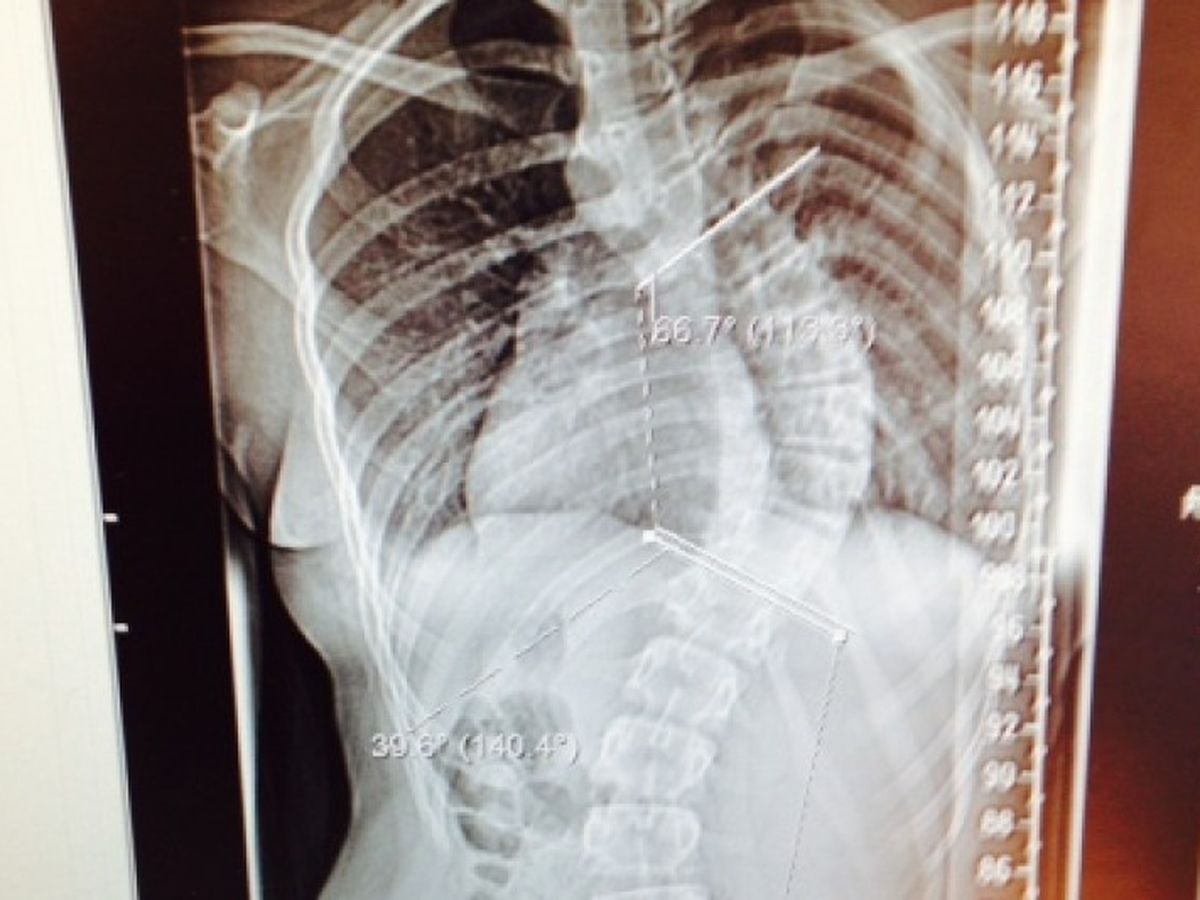

This is a picture of Evie's back. She is 13 years old and was diagnosed last September with severe scoliosis. Evie desperately needs an operation that can only be performed in America and costs over £150,000. We are family friends trying to raise as much as we can to help pay for Evie's vital back operation.